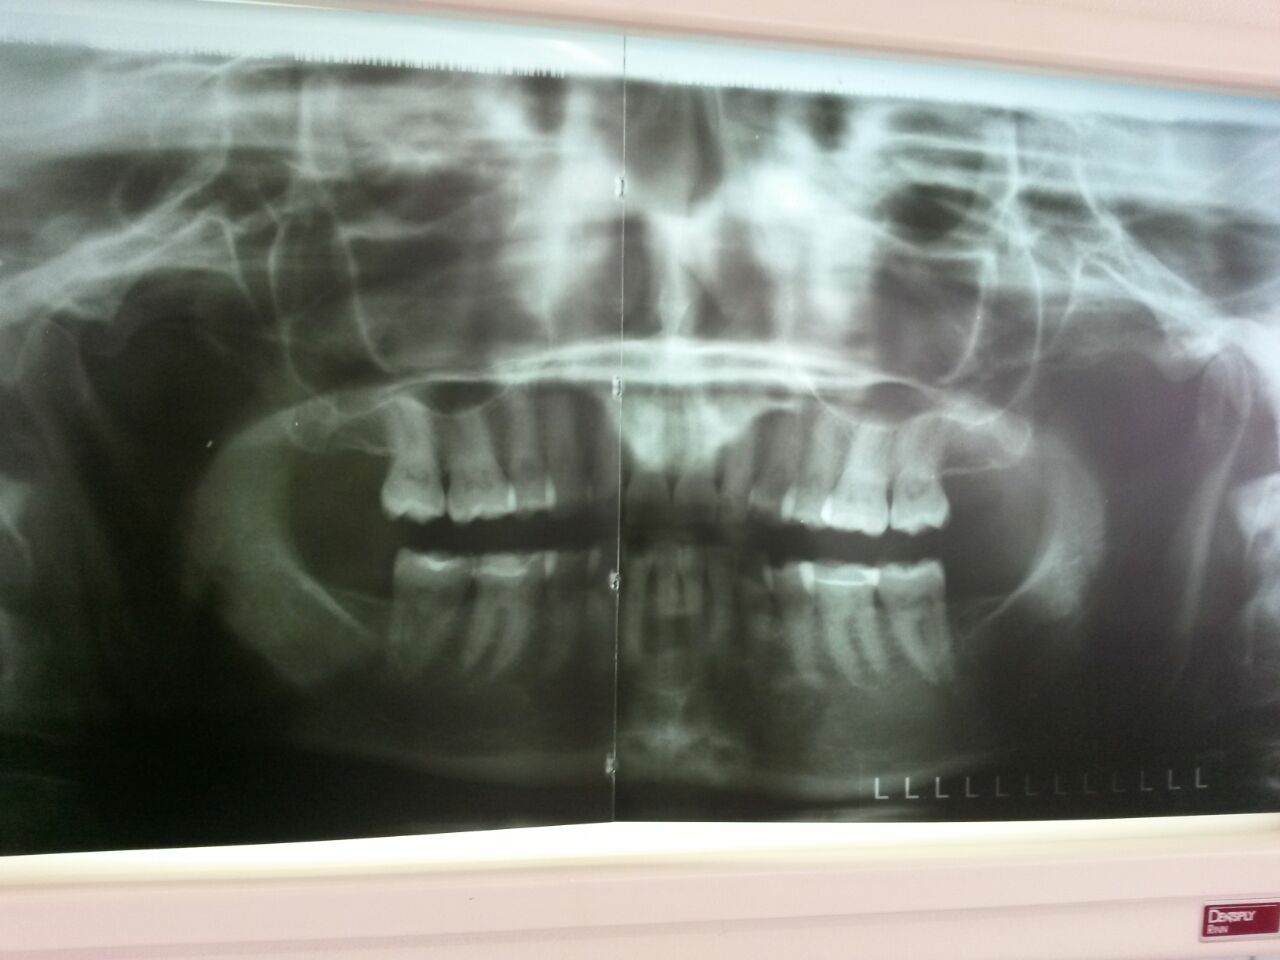

schon der Kier angeschaut? : kieferfehlstellung das kann die ursache von Tinnitus sein!

Ja, ich bekomme nun wegen cmd auch physio und eine Schiene. Der kiefer ist stark nach links verschoben und tinnitus u Verspannungen ist auch alles links. Ich glaube aber das c2 o c4 noch blockiert ist und so eine atlasbehandlung gut wäre. Darf man das machen 2 wochen nach Atlantomed? S. O beschrieben. Ich fände es einen guten Zusatz zur cmd Therapie. Lg milena

Danke Uli für deine Antwort! Der Kiefer ist sehr nach links verschoben bestätigte heute auch die Physiotherapeutin und alles sehr eng aneinander an dieser Seite und unter Spannung.

War gerade bei der Physiotherapie wegen cmd und meine Therapeutin meinte von sich aus dass mein Atlas verschoben ist. Der dornansatz vorne links zu weit vorne ist und hat es korrigiert...ohne knacken sondern ostheophatisch. Beim at war ich vor 2 Wochen zur atlaskorekktur, auch zu weit links vorne war mein Atlas laut at. Wie passen denn die aussagen zusammen ? Eigentlich mĂĽsste mein atlas nach Atlantomed doch korrekt liegen und wie kann man da osteopathisch korrigieren bzw was? Feineinstellung? Sie redete nur v 1mm.